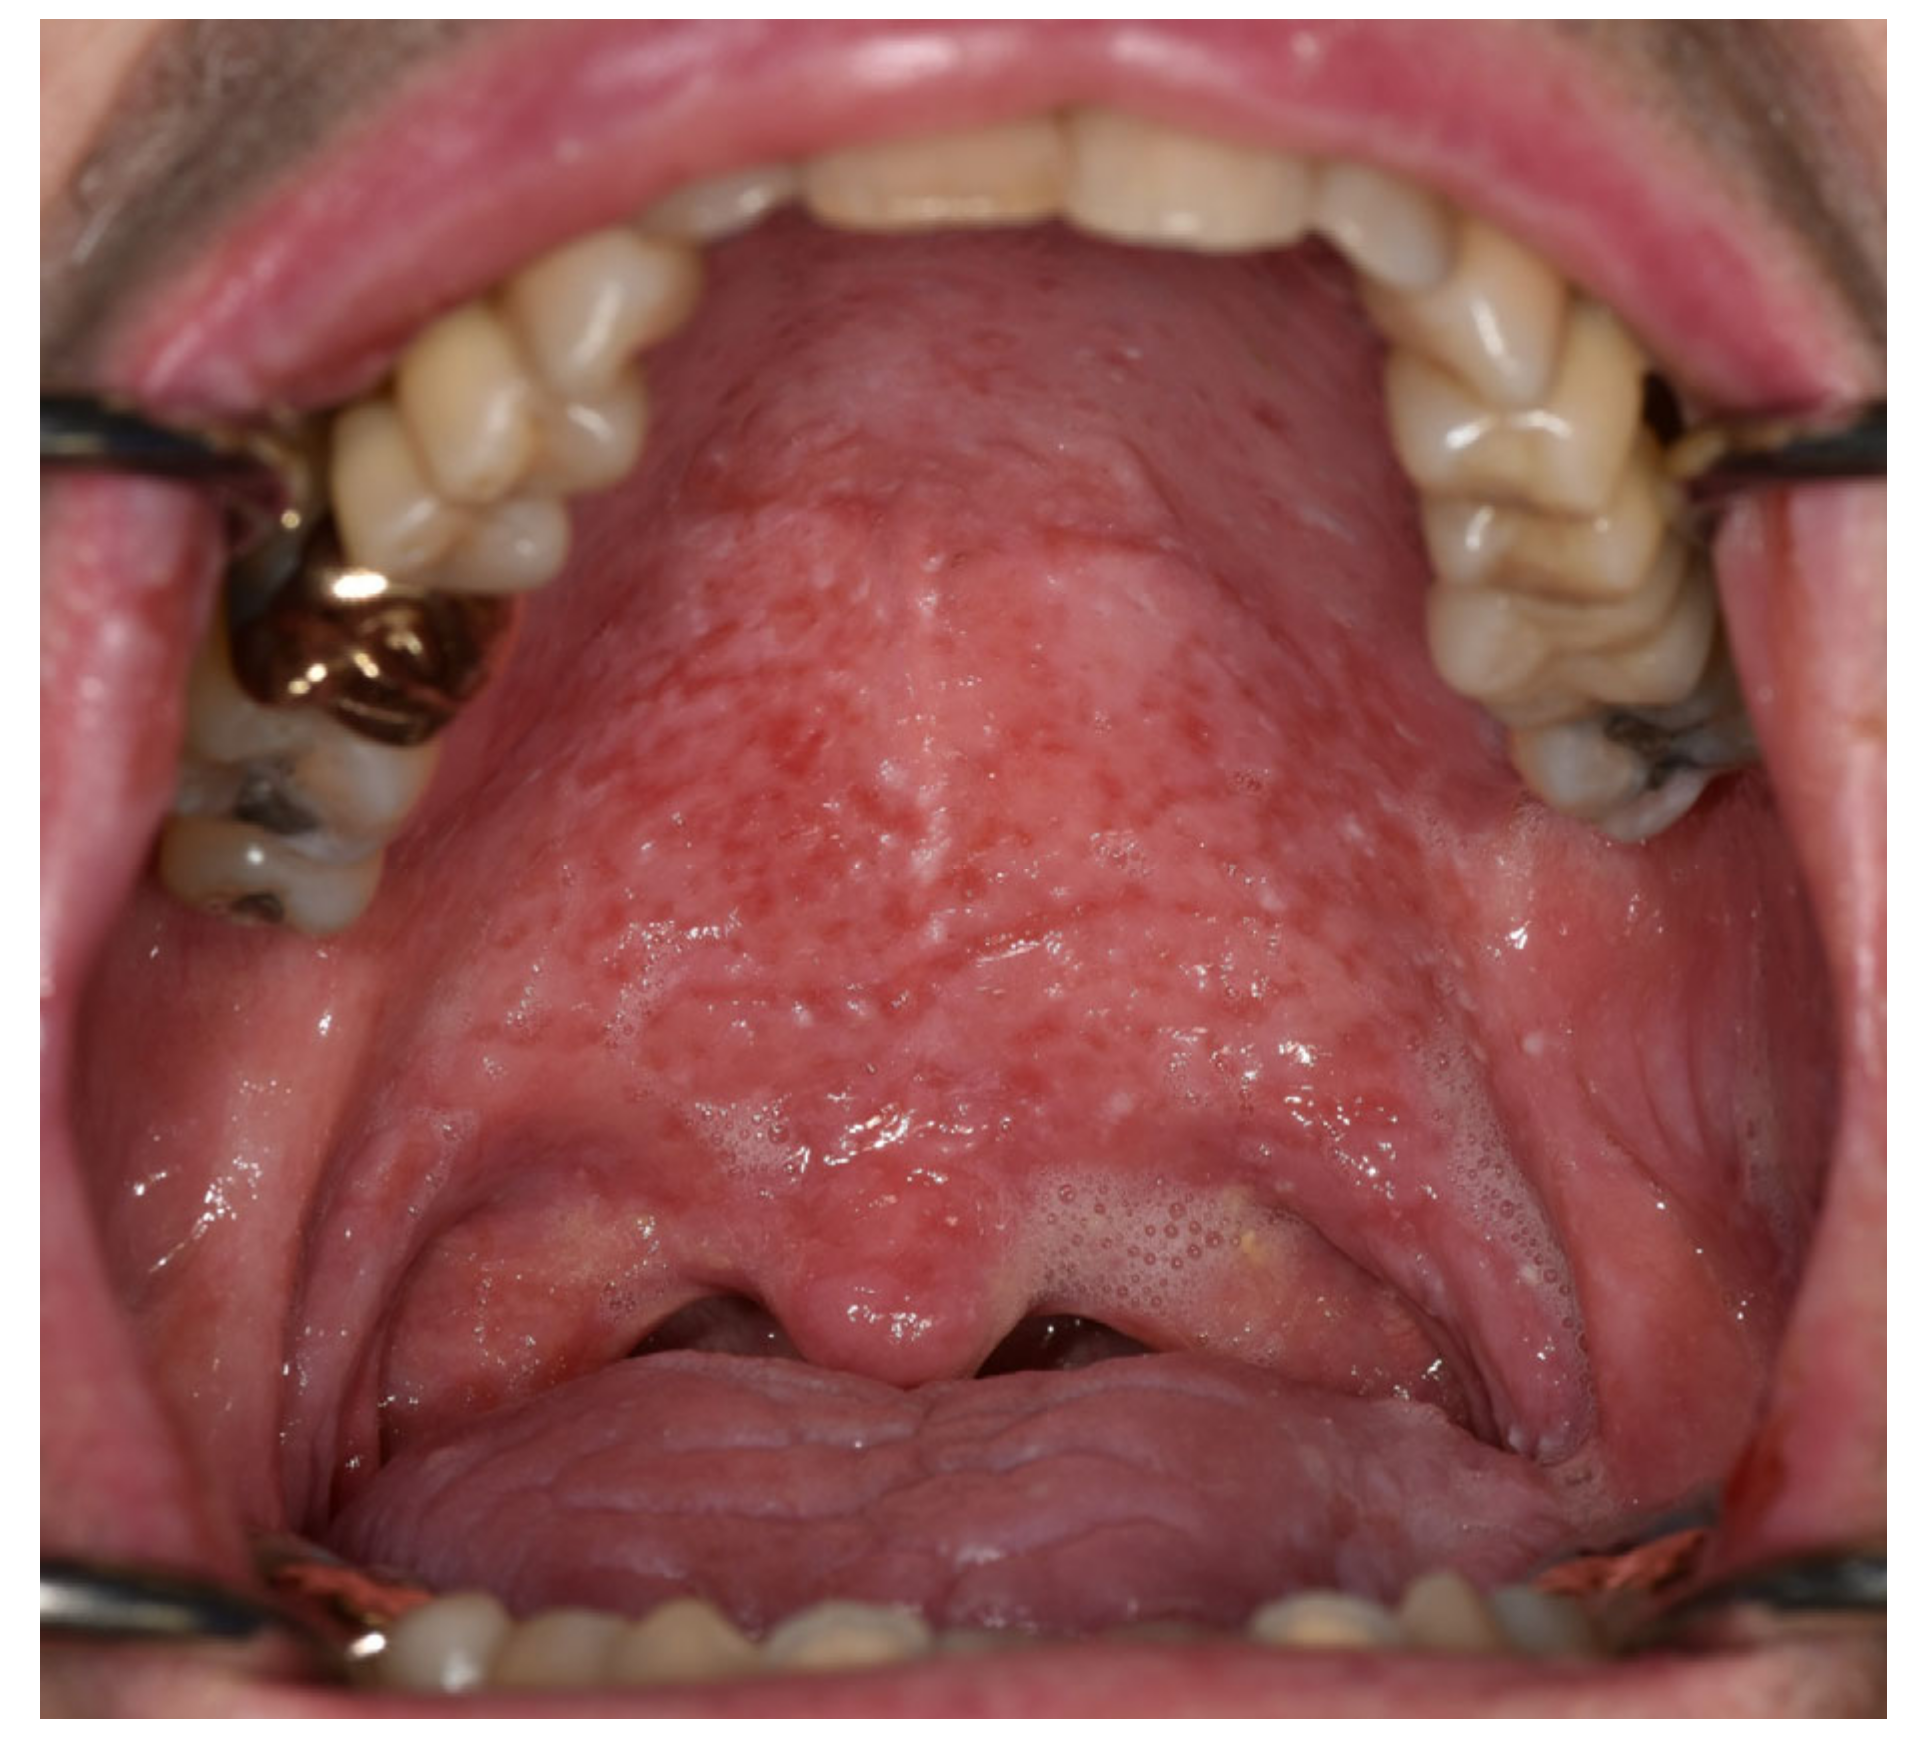

| Signs | Thick, sticky, frothy saliva | Thick, sticky, frothy saliva, glossy appearance, depapillated tongue, oral candidiasis | Glossy appearance | Glossy appearance; mirror sticks to surface | Glossy appearance, sticky saliva | Dry and cracked lips | Thick, sticky, frothy saliva; dry and cracked lips; mucoid strings; glossy tongue appearance, oral surface is wet | Oral surface is very dry |

| Dry mouth (0–10) | 7.5 | 9 | 10 | 9 | 8 | 4 | ||

| Type of symptoms | Xerostomia, loss of appetite, waking from sleep | Dryness, cannot tolerate dry intake, waking from sleep because of xerostomia | Severe dryness, dysphagia, difficulty speaking | Severe dryness | Dryness, dysphagia | Dry lips | Dryness, sticky mucous | |